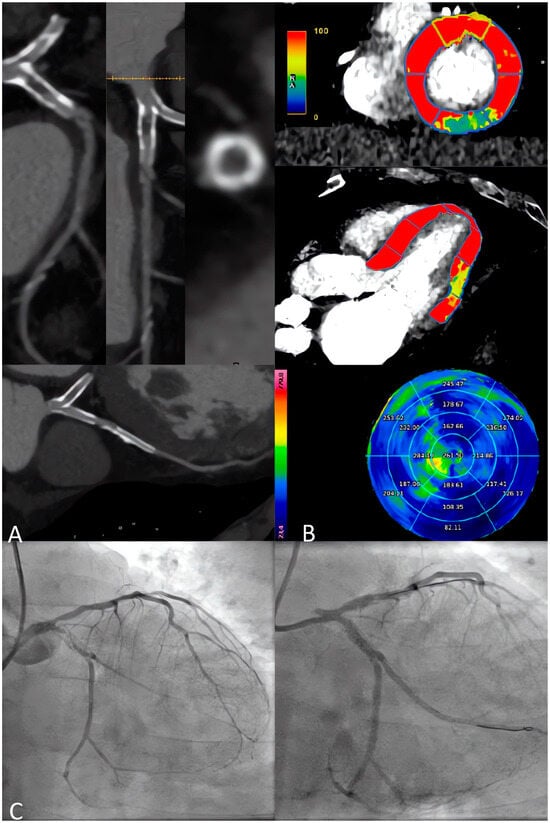

3.2. CCTA in the Planning of PCI